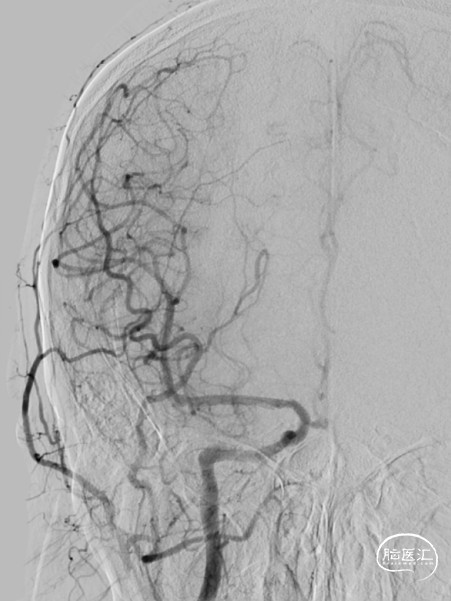

造影提示右侧颈内动脉起始段狭窄,狭窄率约95%,右侧大脑前显影浅淡,前交通开放。左侧颈内动脉通过前交通向右侧大脑前动脉代偿供血。后交通开放,向右侧大脑中动脉代偿供血。

沿导丝置入5*30mm AVIATOR PLUS球囊扩张颈内动脉开口处狭窄病变,后将9*40mm PRECISE支架送至狭窄处释放。再次造影可见右侧颈内动脉血流通畅,但仍有50%左右残余狭窄。

再次应用6*30mmAVIATOR PLUS球囊后扩张,此时患者出现轻度颈动脉窦反应。造影示残余狭窄约30%,支架贴壁良好,血流通畅,颅内血流速度尚可。